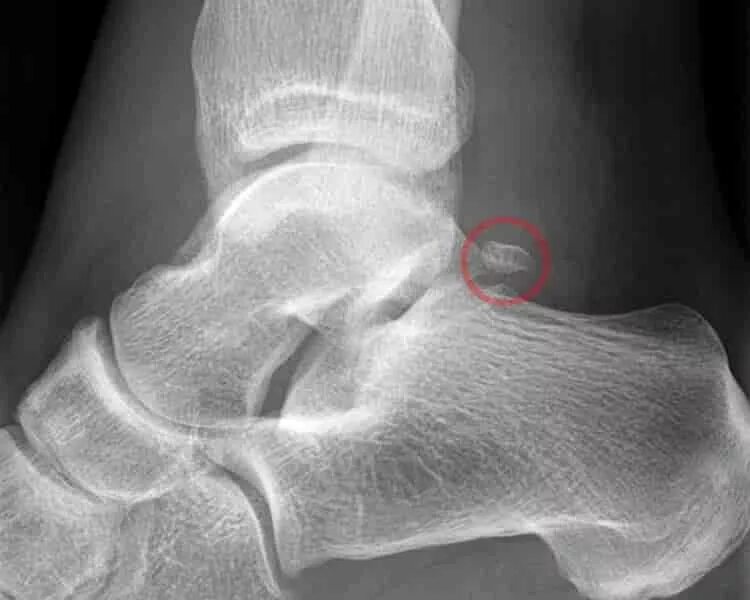

Перелом задней кости стопы